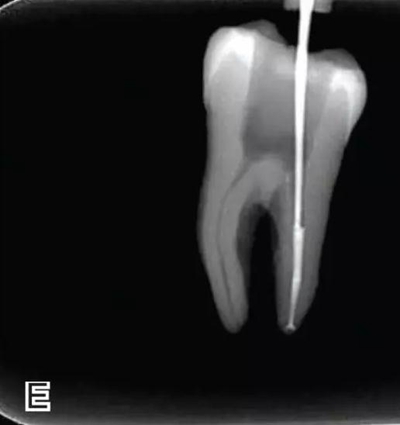

3、試尖

選擇非標(biāo)準(zhǔn)牙膠尖(如0.04、0.06 錐度牙膠尖)作為主尖,型號一般與根管預(yù)備最大號的器械型號一致,能到達(dá)距根尖0.5~1 mm 處,主尖尖段與根管壁緊密接觸。拍試尖X 線片進(jìn)行確認(rèn)(圖3)。

圖3 試尖,A.試主尖 B.拍試尖X片